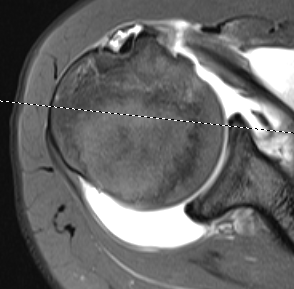

Full thickness minimally retracted subscapularis tear